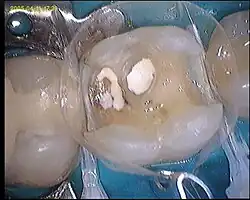

-

1. Zahn mit erneuerungsbedürftiger Füllung -

2. Alte Füllung entfernt -

3. Karies entfernt -

4. Pulpanahe Bereiche mit Ca(OH)2-haltigem Medikament abgedeckt, Ätzgel aufgebracht -

5. Angeätzt, ist die milchige Zone des Schmelzes zu erkennen -

6. Bonding aufgebracht, Matrize und lichtleitende Keile angebracht -

7. Composit in leichtem Überschuss eingebracht -

8. Füllung ausgearbeitet und poliert

Zunächst wird wie bei jeder Füllung eine etwaige alte Füllung (Bild 1) sowie die Karies (Bild 2) entfernt (Bild 3). Die Kavität wird durch Ätzung des Schmelzrandes mit hochprozentiger Phosphorsäure (35–37 %) vorbereitet (Bild 4). Durch die Freilegung der Schmelzprismen wird die Verbindung zwischen Zahn und Füllungsmaterial verbessert, sichtbar in der milchigen Oberfläche des sonst hochglänzenden Zahnschmelzes (Bild 5). Nach Spülung und Trocknung der Kavität wird auf das Geflecht aus Kollagenfasern der Primer, Hydroxyethylmethacrylat (HEMA) gegeben, der sowohl hydrophil, als auch hydrophob ist. Anschließend wird ein dünnflüssiges Monomer (Bonding) (Bild 6) aufgebracht und mit blauem Licht polymerisiert. Die Komposite werden anschließend schichtweise in die Kavität eingebracht und mit blauem Licht (Halogen- oder LED-Lampe) ausgehärtet (Bild 7). Das schichtweise Vorgehen verhindert die Bildung von Randspalten infolge der unvermeidlichen Polymerisationsschrumpfung des Kunststoffs. Abschließend erfolgt die Formgebung und Abtragung von Kunststoff-Überschüssen mit Schleifkörpern, sowie die Politur (Bild 8).